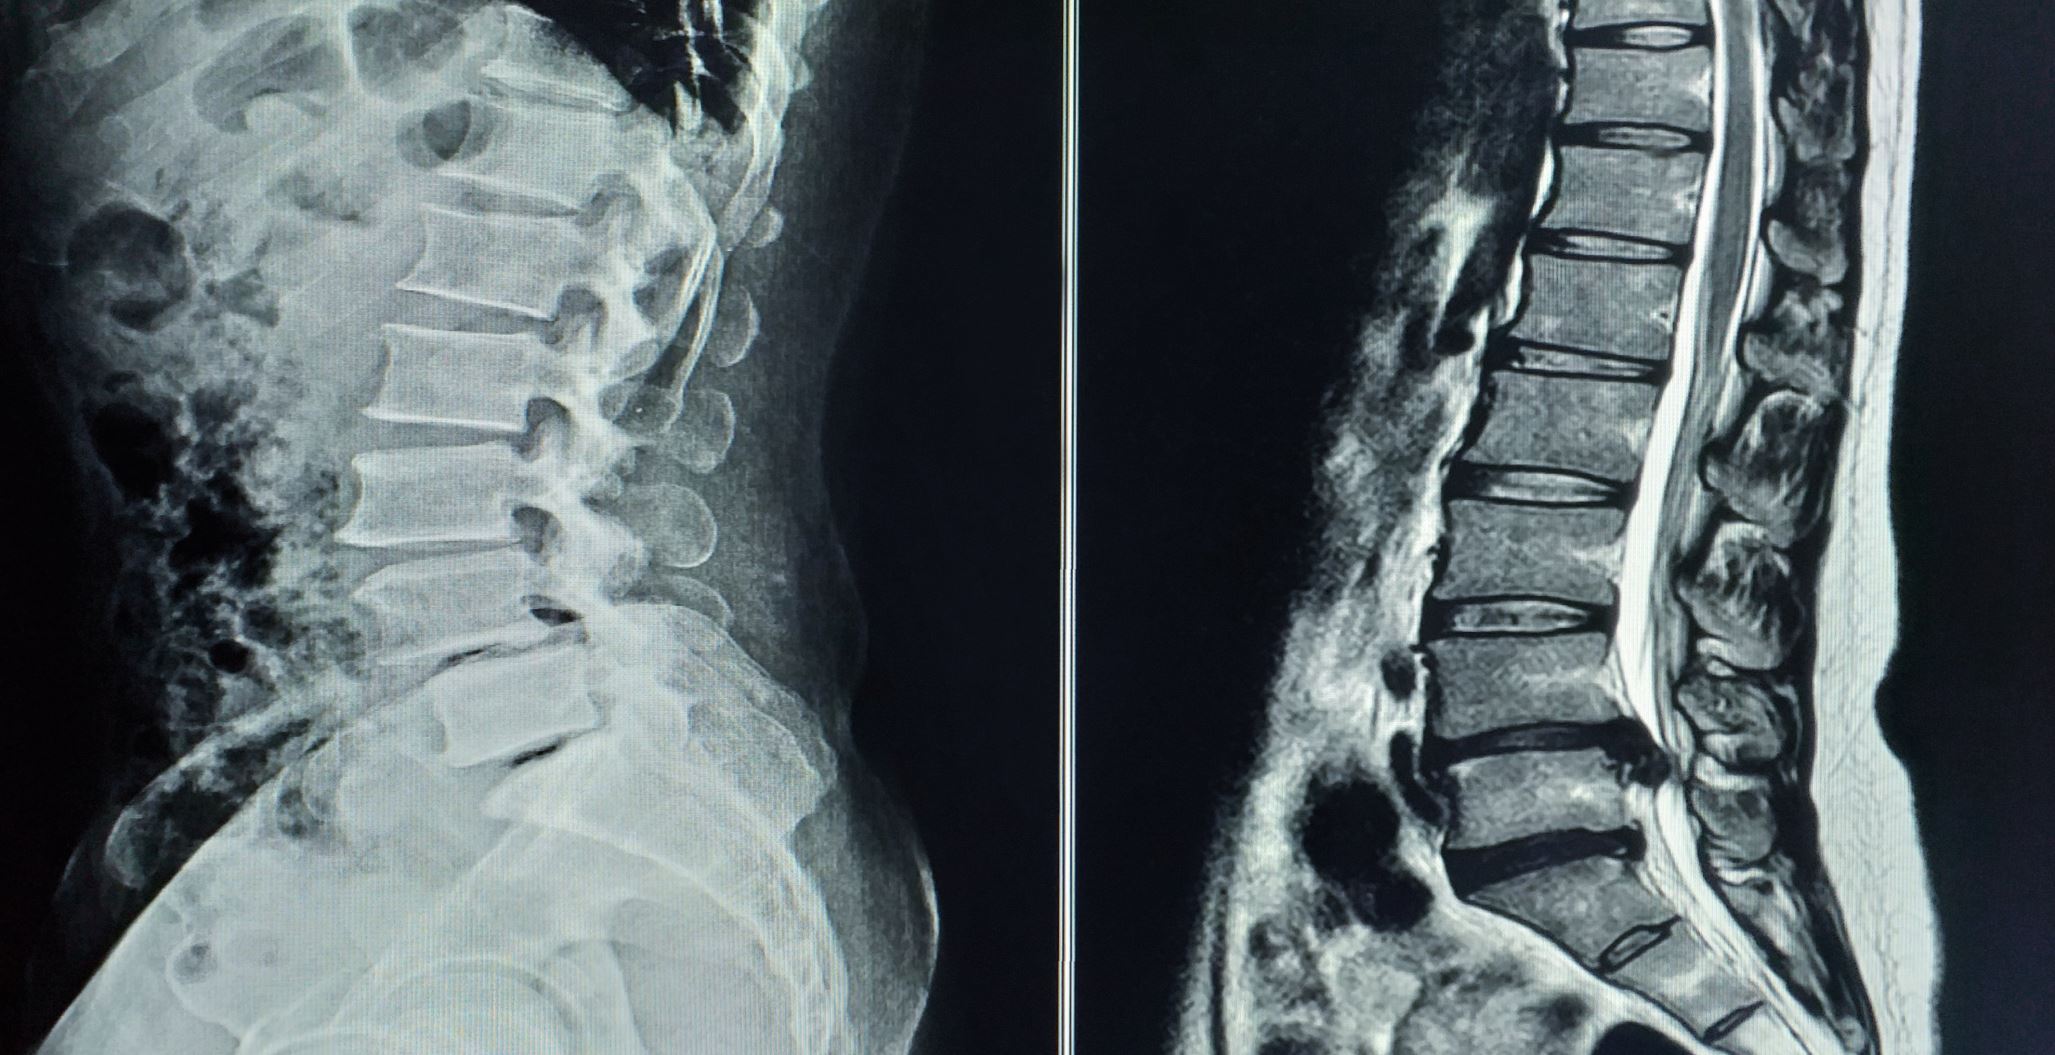

Das "Bewegungssegment" als kleinste Einheit für den funktionalen Aufbau der Wirbelsäule besteht jeweils aus zwei Wirbeln und der dazwischenliegenden Bandscheibe. Neben der Bewegungsfunktion haben die Bandscheiben eine Pufferfunktion und gewährleisten die Druckverteilung innerhalb des Bewegungssegmentes. Die Bandscheiben bestehen aus einem gallertartigen Kern, dem Nucleus pulposus, und dem äußeren Faserring Anulus fibrosus. Bandscheibendegenerationen beziehungsweise -vorfälle können prinzipiell in jedem Wirbelsäulenabschnitt auftreten. Epidemiologische Praxisstudien zeigen, dass 36 % der Erkrankungen auf die Halswirbelsäule, 62 % auf die Lendenwirbelsäule und 2 % auf die Brustwirbelsäule entfallen. In Abhängigkeit von der Lokalisation verursachen Bandscheibenvorfälle unterschiedliche Beschwerden und haben unterschiedliche therapeutische Konsequenzen.

© Richman Photo / stock.adobe.com